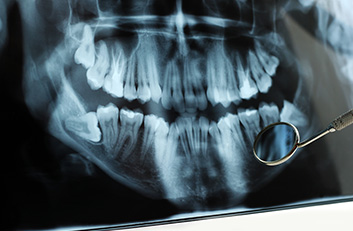

La endodoncia le da más tiempo de vida útil a su pieza dental, en Dental Evolution Cancún le recomendamos evitar la extracción realizándose este procedimiento que garantizamos será sin dolor, gracias a la tecnología de vanguardia con la que contamos, instrumental rotatorio, sistema de ultrasonido, y a nuestra “radiografía digital” la cual juega un papel crucial en el procedimiento de endodoncia, además de que usted estará atendido con la calidez, calidad humana y  profesionalismo que caracteriza a nuestro experto equipo de dentistas  especializados que le apoyaran en todo momento.